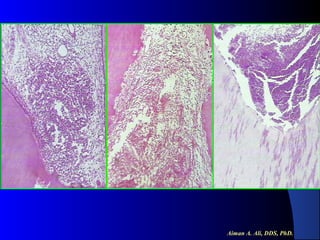

Chronic Pulpitis

 Histopathological

Features:

Mononuclear inflammatory cell

infiltration.

 Evidence of fibroblastic activity.

 Minute abscess if exist it is localized

by granulation tissue.

Chronic Hyperplastic Pulpitis

Pulp Polyp

polyp consists of granulation tissue.

It contains delicate connective tissue, fibers

and blood vessels.

Mononuclear inflammatory cell infiltration.

The polyp is covered with SS epithelium.